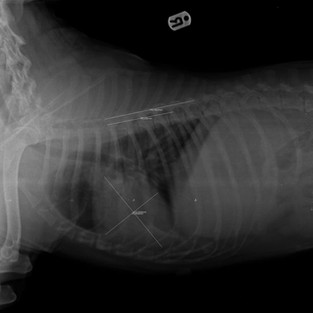

XRAY RESULTS of Tyson

Radio opaque in chest cavity, heart covered either with fluid or blood, bloody pee, Diaphragma still intact, intestines normal, spine looks ok, but not sure if there is any compression dx RTA, pneumothorax due to accident, spinal compression